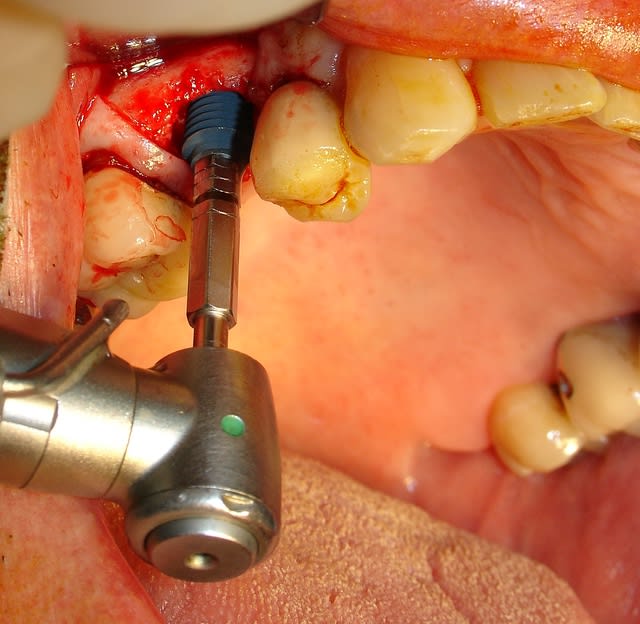

Le remplacement c'est fait par un AnyRidge de chez MegaGen de diamètre 5 et longueur 10. J'ai juste profiter de la situation pour re-combler là ou en 2007 on avait mis de l'os autogène....mais ou est il passé? Le comblement a été fait avec une recette maison à base de PRF os bovin et bétaTCP.